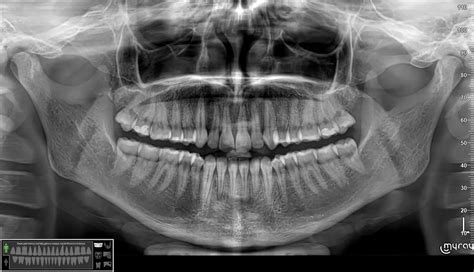

- Radiologiniai tyrimai, tokie kaip rentgeno nuotraukos, yra būtini cistų matavimui ir jų lokalizacijai nustatyti.

Tipiški dantenų ligų simptomai apima dantenų paraudimą, patinimą, jautrumą, lengvą kraujavimą plaunant dantų šepetėliu ar valgant, taip pat blogą burnos kvapą. Dantenų ligų diagnozavimas prasideda nuo išsamaus burnos patikrinimo, kurį atlieka odontologas. Gydytojas įvertina dantenų būklę, dantenų kišenių gylį, taip pat apnašų ir dantų akmenų buvimą. Siekiant gauti tikslesnę informaciją, gali būti atliekamos rentgeno nuotraukos. Tai padeda nustatyti, ar nėra kaulų nykimo požymių, kurie būdingi periodontitui.